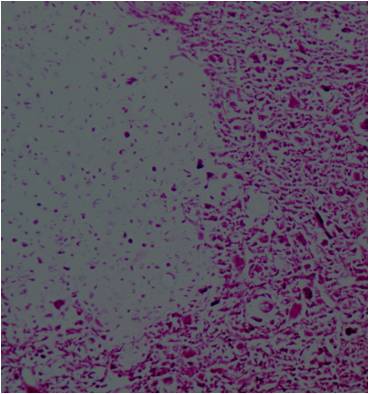

- Neoplastic cells may be small, round, oval, or spindle shaped

- Undifferentiated mesenchymal cells similar to Ewing sarcoma

- Low grade islands of cartilage scattered throughout the mesenchymal cells

- Usually only a small part of lesion

- Cytologically low grade

- Usually sharply demarcated from surrounding stroma

- May contain islands of collagen resembling osteoid

- Lesions are vascular and often have large, anastomosing vessels that impart hemangiopericytoma-like pattern

(Right Arrow) Cartilaginous Component